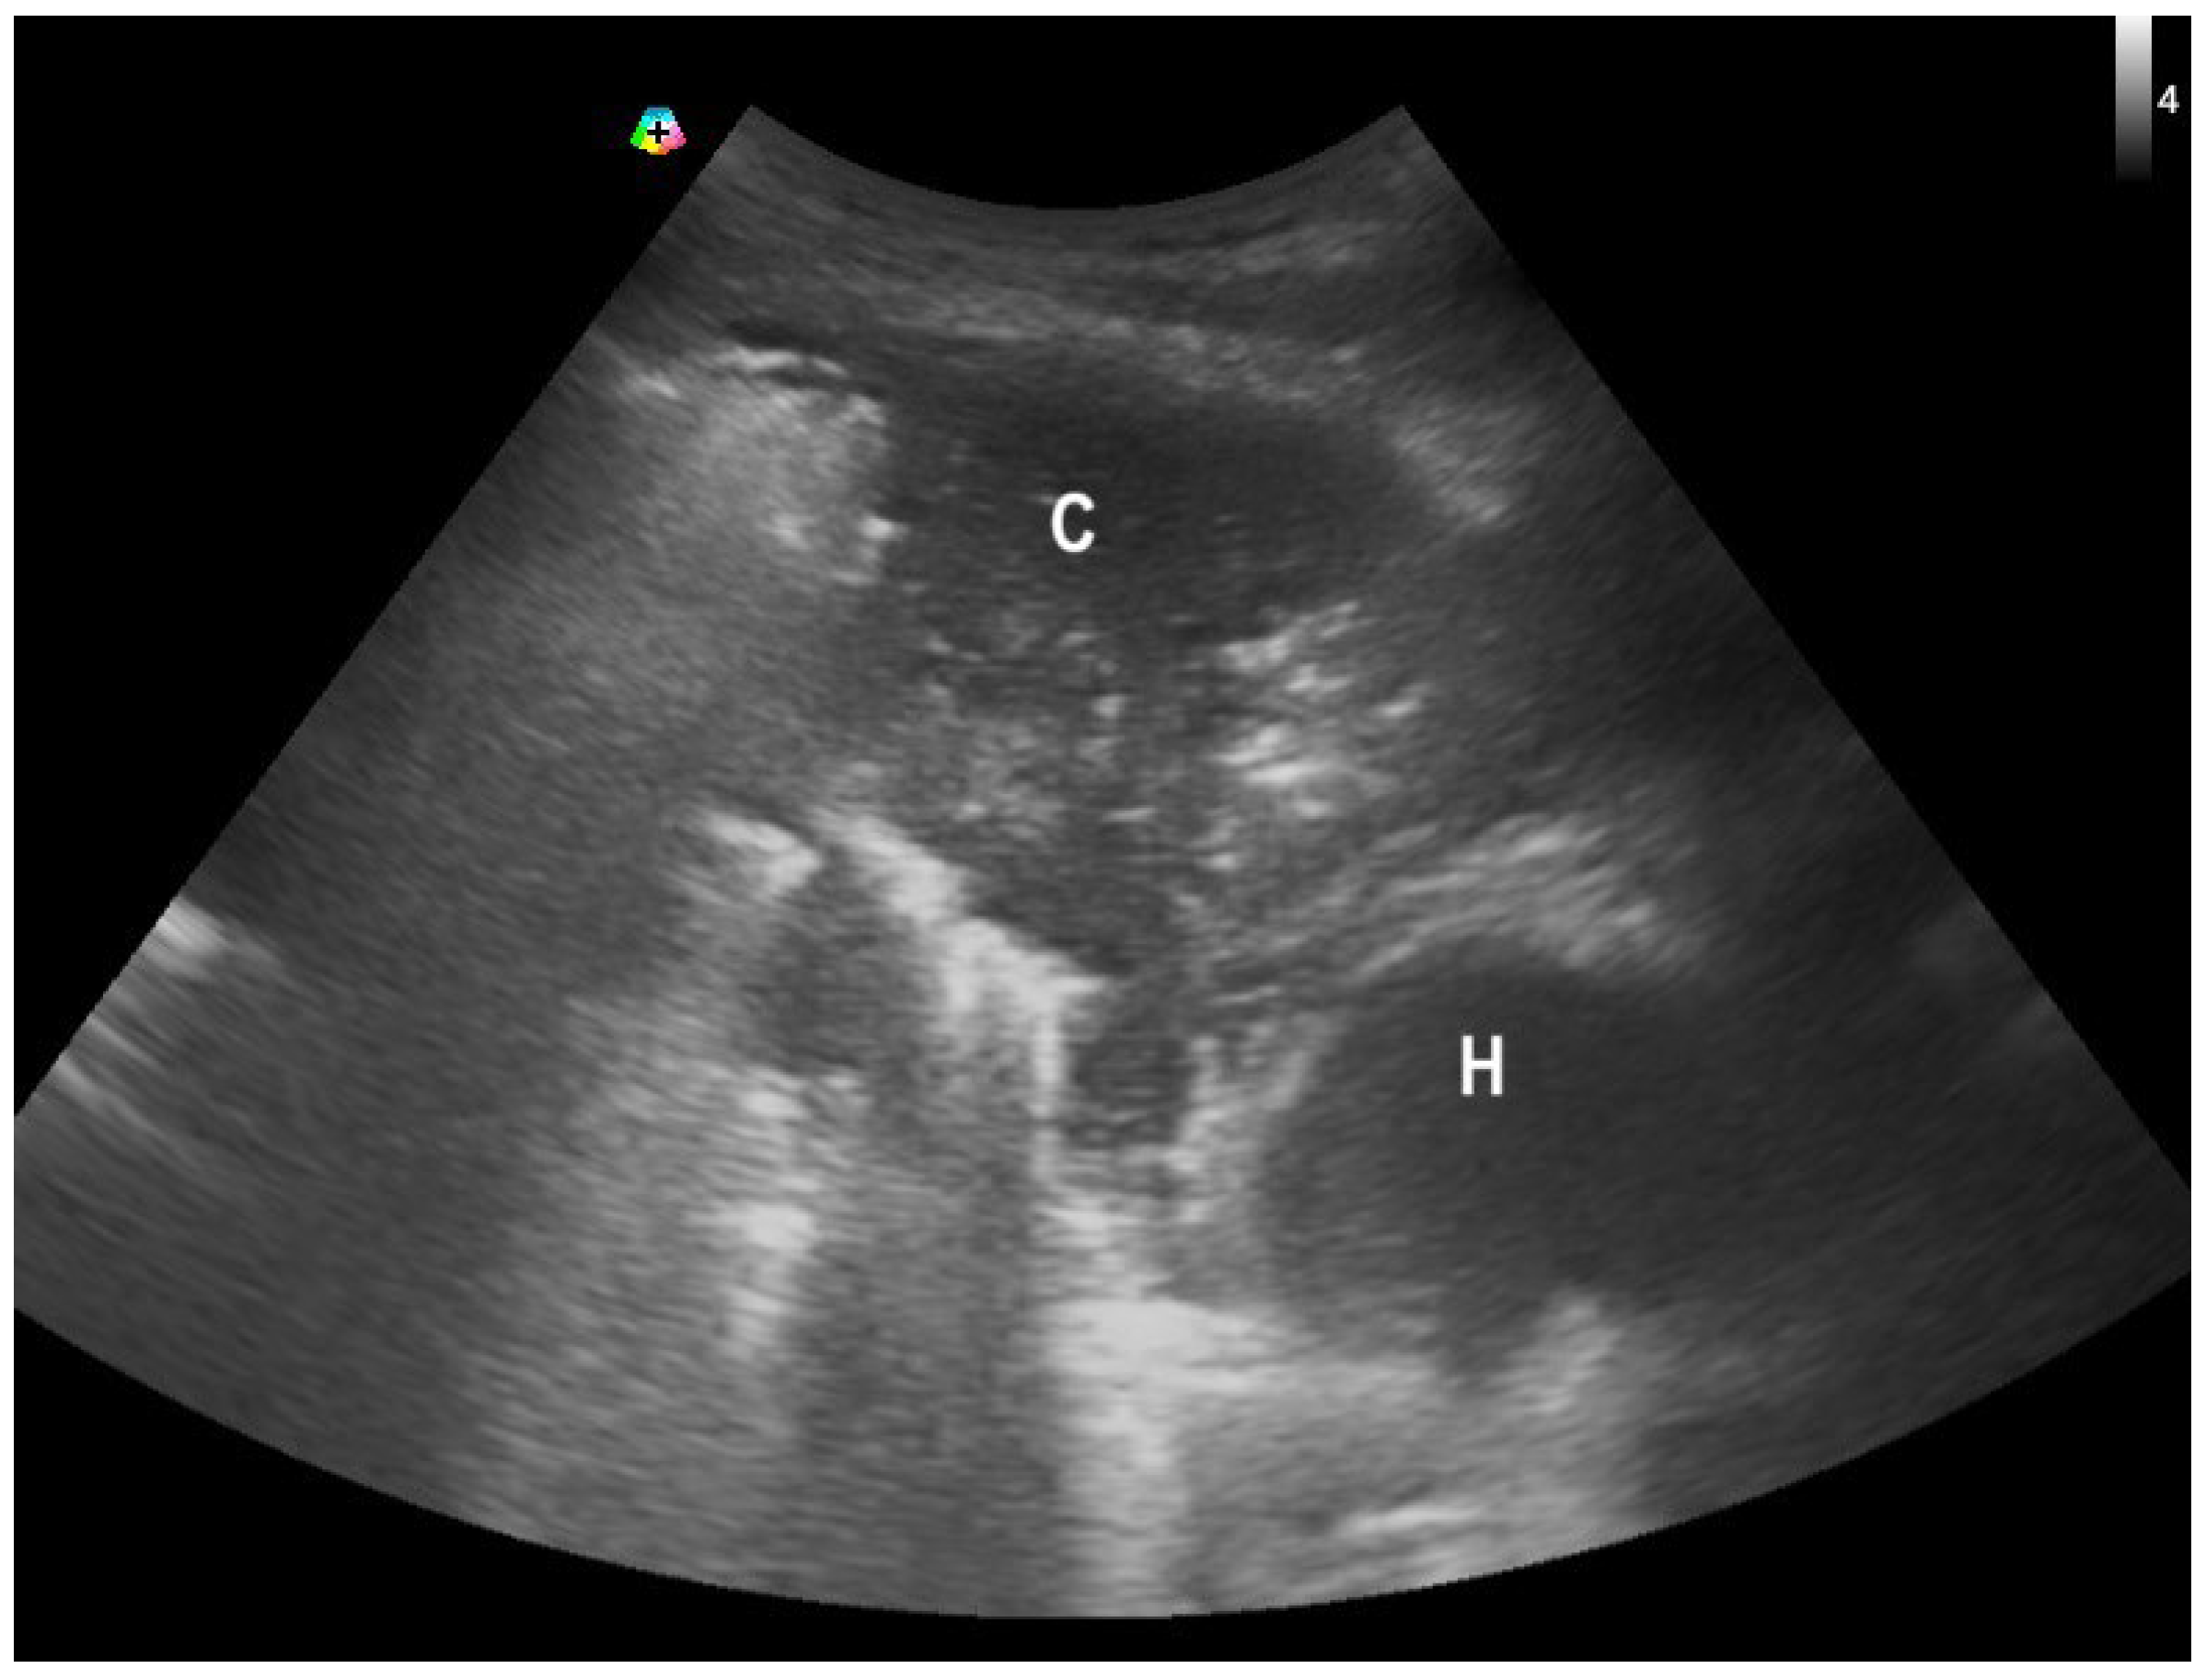

- Hsu, N.C.; Tseng, C.L.; Yang, C.W.; Hsu, C.H. Man With Dyspnea. Ann Emerg Med. 2022, 79, e105–e106. [Google Scholar] [CrossRef]